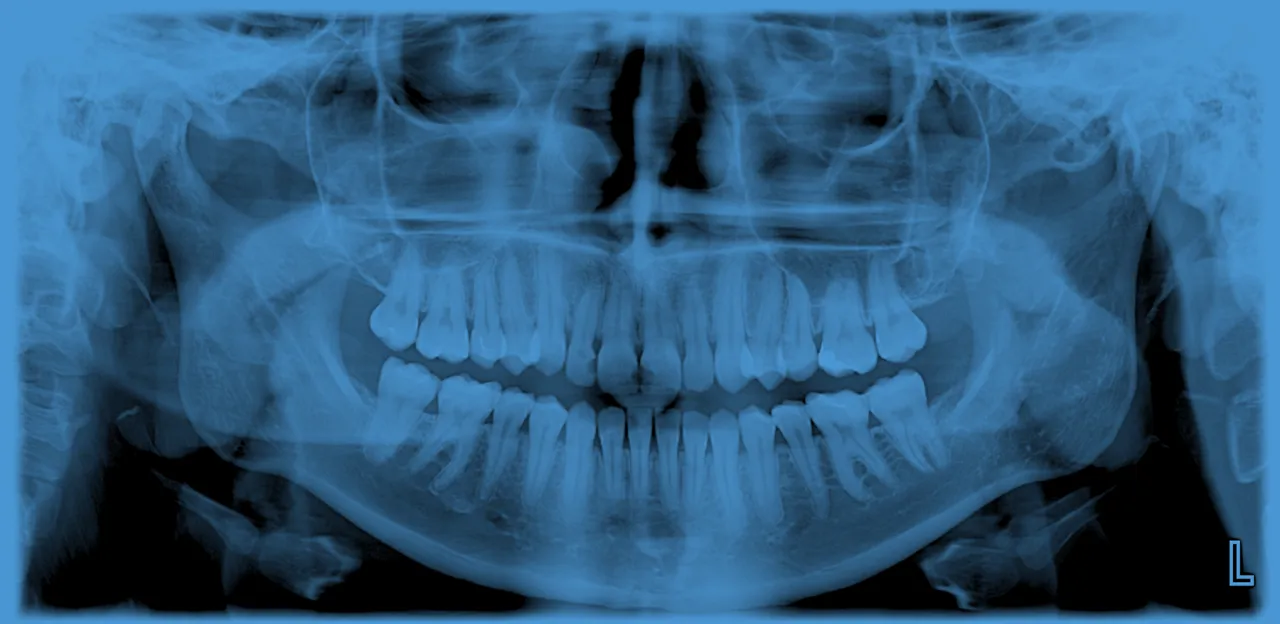

Zdjęcie panoramiczne zębów, znane również jako pantomogram lub OPG (Orthopantomogram), to rodzaj zdjęcia rentgenowskiego, które daje lekarzowi stomatologowi szeroki obraz sytuacji w jamie ustnej. Na jednym, kompleksowym zdjęciu widoczne są wszystkie zęby zarówno te wyrznięte, jak i te jeszcze niewyrżnięte czy zatrzymane. Obejmuje ono również całą kość szczęki i żuchwy, a także stawy skroniowo-żuchwowe oraz zatoki szczękowe. Dzięki temu pantomogram jest niezwykle cennym narzędziem diagnostycznym, pozwalającym na ocenę stanu całego uzębienia i kości, a nie tylko pojedynczych obszarów.

Główna różnica między zdjęciem panoramicznym a zwykłym zdjęciem rentgenowskim zęba tkwi w zakresie obrazowania. Zwykłe zdjęcie RTG skupia się na jednym lub kilku zębach, pokazując ich korzenie i otaczającą tkankę kostną w bardzo szczegółowy sposób. Jest to badanie punktowe, idealne do diagnozowania konkretnego problemu, jak np. zapalenie korzenia czy głęboka próchnica. Natomiast pantomogram, jak sama nazwa wskazuje, daje obraz panoramiczny obejmuje całe uzębienie, obie szczęki, żuchwę i stawy skroniowo-żuchwowe na jednym zdjęciu. Dzięki temu pozwala na ocenę ogólnego stanu zdrowia jamy ustnej, wykrycie nieprawidłowości w rozwoju zębów, ocenę stanu kości, a także zaplanowanie kompleksowego leczenia, które może obejmować wiele zębów lub wymagać interwencji chirurgicznej.

Ukryta próchnica, zęby zatrzymane i stany zapalne: co pokaże prześwietlenie?

- Ukryta próchnica: Szczególnie próchnica międzyzębowa, która jest trudna do wykrycia podczas rutynowego badania.

- Zęby zatrzymane: Na przykład zęby mądrości, które nie wyrosły prawidłowo i mogą powodować problemy.

- Stany zapalne: Zapalenie kości, ropnie okołowierzchołkowe, torbiele czy zmiany zapalne w obrębie stawów skroniowo-żuchwowych.

- Choroby przyzębia: Zaawansowanie paradontozy i utratę kości wokół zębów.

- Urazy: Pęknięcia korzeni, złamania kości szczęki lub żuchwy.

- Nieprawidłowości w budowie kości: Guzy, torbiele czy wady rozwojowe.

Zdjęcie panoramiczne jest absolutnie kluczowe przy planowaniu wielu złożonych procedur stomatologicznych. W przypadku leczenia ortodontycznego pozwala ocenić położenie wszystkich zębów, w tym tych zatrzymanych, stan kości szczęki i żuchwy, a także symetrię twarzoczaszki. Jest to niezbędne do dobrania odpowiedniego aparatu i strategii leczenia. Podobnie w przypadku implantologii pantomogram dostarcza informacji o ilości i jakości kości w miejscach planowanego wszczepienia implantów, co jest kluczowe dla sukcesu zabiegu. Jest również nieocenione w chirurgii stomatologicznej, np. przed skomplikowanym usunięciem zębów mądrości.